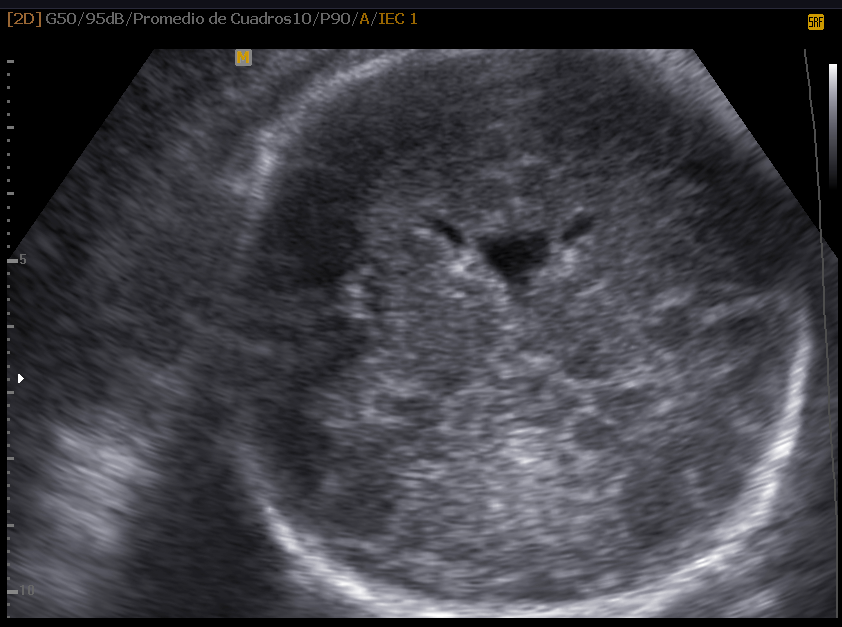

La Neurosonografía Fetal se refiere a la evaluación del Sistema Nervioso Central por Ultrasonidos: cráneo y su contenido (cerebro, ventrículos, tallo, cerebelo, etc.) y de la columna vertebral y su contenido (vértebras, médula espinal, líquido cefalorraquídeo, etc.).

La determinación de la normalidad anatómica depende de la etapa del desarrollo en la que se pretende estudiar en contenido encefálico y del momento de aparición de las anomalías posibles; además, a diferencia de otros órganos cuya estructura madura es bastante estable y resistente a agresiones durante el embarazo, el contenido craneal puede verse afectado en cualquier etapa del embarazo, durante el nacimiento y en vida posnatal.

Las estructuras intracraneales después de la semana 18-20 del embarazo son muy características y permanecen visualmente invariables hasta el final del embarazo, solo modificando sus tamaños a medida que el feto crece. Esto es de gran ayuda ya que permite determinar la aparición de cambios que podrían sugerir desviación de la normalidad y aparición de una malformación congénita o lesión adquirida por eventos externos especialmente relacionados a infecciones y accidentes vasculares fetales.